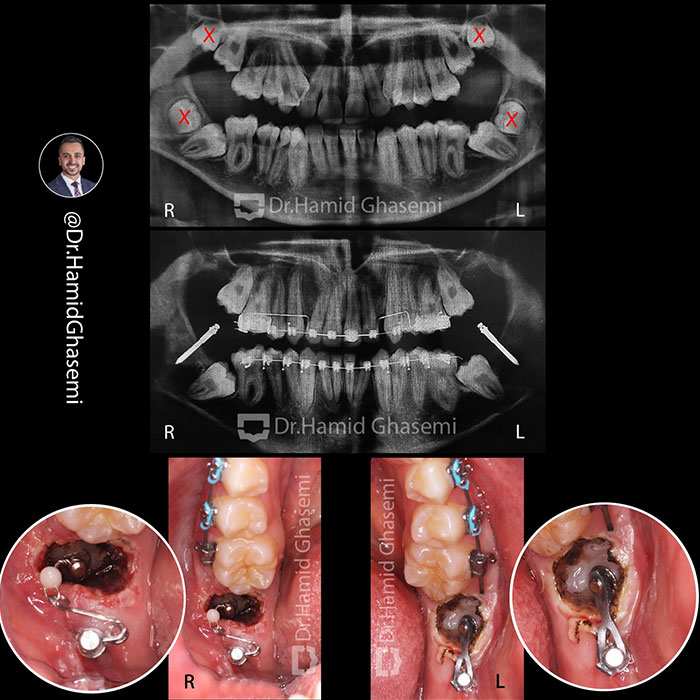

ارتودنسی مولتی لوپ؛ درمان تخصصی ناهنجاریهای فک و دندان11 آذر 1403 - 10:24 ق.ظ

ارتودنسی دندان نهفته؛ راهحلی برای درمان مشکلات پنهان دندانها10 آذر 1403 - 6:20 ب.ظ